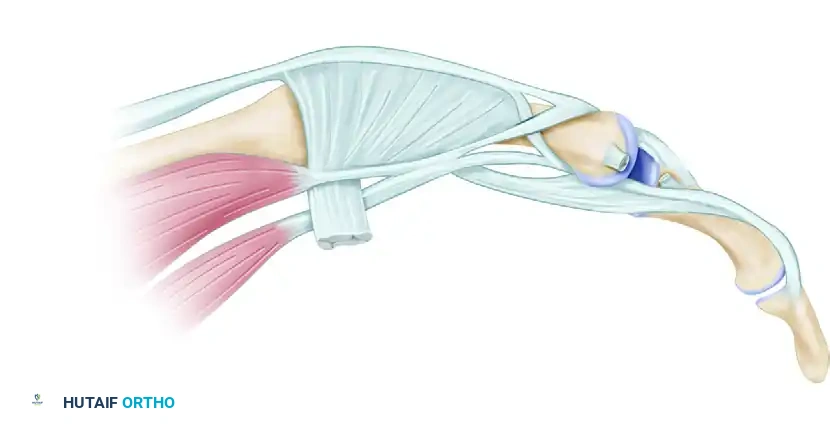

The rheumatoid hand frequently presents with a complex, progressive deformity characterized by volar subluxation and ulnar drift of the metacarpophalangeal (MCP) joints. This pathognomonic cascade is initiated by chronic synovitis, which distends the joint capsule, attenuates the collateral ligaments, and destroys the articular cartilage. As the radial sagittal band becomes attenuated by the expanding synovial pannus, the extensor digitorum communis (EDC) tendon subluxates into the ulnar valley between the metacarpal heads.

Once the extensor tendon falls ulnar to the axis of rotation, it ceases to function as an MCP joint elevator and instead becomes a paradoxical deforming force, exacerbating both ulnar deviation and volar subluxation. Concurrently, the intrinsic muscles—particularly the ulnar intrinsics—contract and shorten, further tethering the proximal phalanx into ulnar deviation. The long flexor tendons, acting across the palmar aspect of the joint, also bowstring ulnarly, exerting a massive palmar and ulnar-directed vector that ultimately leads to frank MCP joint dislocation.

2. Extensor Hood Release and Arthrotomy

- Radial Incision: Enter each MCP joint through a longitudinal incision on the radial side of the extensor hood, parallel to the extensor tendon.

- Mobilization: Dissect the extensor hood from the underlying joint capsule. This step is crucial to release the ulnarly displaced extensor mechanism, allowing it to be mobilized back to the dorsal midline.

- Capsulotomy: Make a longitudinal incision in the dorsal capsule.

> Surgical Warning: Ensure the capsular incision does not lie directly deep to the tendon incision. Offsetting these incisions prevents adherence of the extensor tendon to the joint capsule during the healing phase, which would severely restrict active flexion.